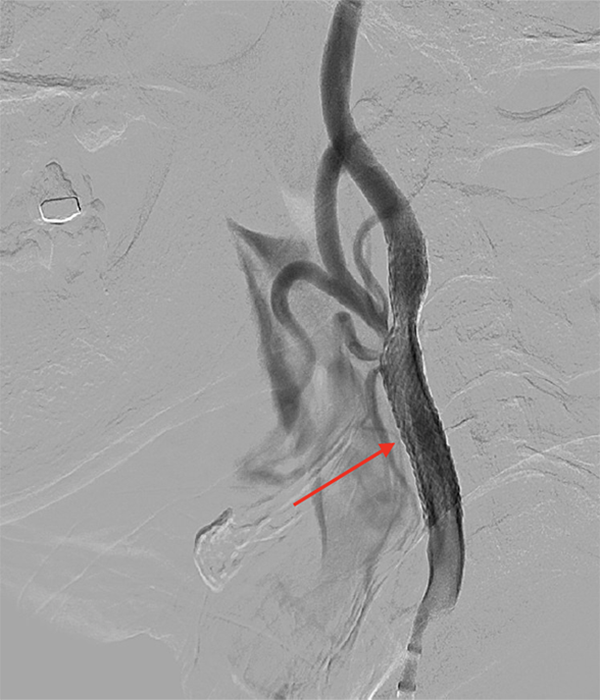

手術方法

局所麻酔で行います。

- 足の付け根の動脈(大腿動脈)からカテーテルを挿入します。

- フィルターやバルーンで血栓が脳へ飛ばないよう保護します。

- 狭窄部をバルーンで拡張します。

- ステント(金属の筒)を留置し、血流を改善します。

体への負担が比較的少ない低侵襲治療です。

実際の症例